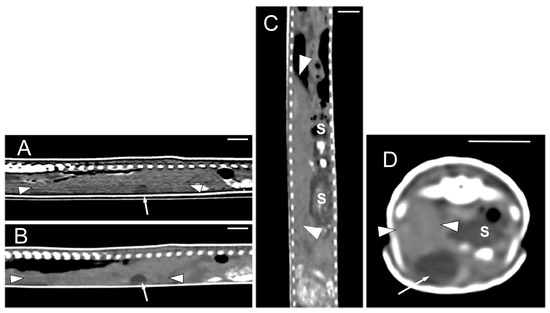

Concerning the CT images, the bifurcation of the trachea into the main bronchi was most clearly observed in the transverse plane (Figure 8A). The two lungs appeared as elongated structures with a reticular hypoattenuating area around an air-filled cavity. The distinction between the hypoattenuating area and just air was more distinctly identified in the transverse and dorsal planes using a postprocessing lung algorithm (Figure 8B,C). The 3D volume rendering using a postprocessing airways algorithm detailed the trachea and lungs (Figure 8D,E). Between the lungs, it was possible to identify those esophageal segments containing gas. On the contrary, those esophageal segments without intraluminal gas were indistinguishable from the surrounding soft tissues. The transverse and dorsal planes were the most useful for recognizing the esophagus (Figure 9). The liver appeared as an elongated organ with soft tissue attenuation located ventral to the caudal midsection of the lungs, on the right side of the stomach. Its margins were not well defined. The gall bladder was identified in the ventral part of the coelomic cavity as a hypoattenuating small oval structure surrounded by the hepatic parenchyma (Figure 10A). The differentiation between the gall bladder and the hepatic parenchyma was more evident in the postcontrast studies (Figure 10B–D). As in the case of the esophagus, the stomach and the small and large intestines were easily distinguished when containing intraluminal gas (Figure 11A) or hyperattenuating content (residual ingesta) (Figure 11B). The small and large intestines were located just caudal to the liver and the stomach, occupying approximately the caudal third of the coelomic cavity. The spleen and pancreas could not be identified when using CT.

Figure 10.

The CT images of Pseudopus apodus in the sagittal (A,B), dorsal (C) and transverse (D) planes showing the liver (between arrowheads) and gallbladder (arrow). Image (A) was obtained precontrast administration and images (B–D) were obtained postcontrast. The contrast enhancement of the normal hepatic parenchyma improved the differentiation between it and the gall bladder and between the liver and stomach (S). Bar = 10 mm.

Although we could identify the liver, the margins of the organ could not be clearly distinguished in precontrast images. The gall bladder was differentiated as a small hypoattenuating structure surrounded by hepatic parenchyma. The difference in attenuation between them was more evident in postcontrast images. It has been reported that the liver lobes and the gallbladder can be distinguished in normal loggerhead sea turtle CT images, although the distinction between the hepatic parenchyma and pectoral musculature may not be clear due to lack of contrast [29]. In a study performed with green iguanas, black and white tegus, and bearded dragons the liver was clearly distinguishable from the surrounding fat bodies. The gallbladder was identified in the three species as well [34]. Nardini et al. [35] evaluated the liver parenchyma and perfusion using dynamic contrast-enhanced computed tomography in captive green iguanas. They reported that unenhanced CT scans provided an excellent visualization of the lizard’s liver, while contrast-enhanced CT permitted further investigation of hepatic perfusion. Sochorcová et al. [37] also studied the feasibility of contrast-enhanced CT for the liver, the gallbladder, and the urogenital tract in red-eared terrapins. These authors determined that the maximum contrast enhancement of the liver was detected 60 s after the contrast injection. In our study, we saw the liver located ventral to the lung, on the right side in relation to the stomach and cranial to the intestines. Melero et al. [42] used the same anatomic landmarks to delineate the hepatic parenchyma as well as the cardiac apex in chameleons, which is just cranial to the liver in this reptile. In some reptiles, contrast-enhanced CT allows to differentiate a thin gallbladder wall [37,42], which we could not distinguish in our study.